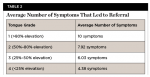

Combining the symptoms and functional grade using the TRQ revealed that 26.1% of children's parents were interested in a referral for further evaluation and possible treatment of a significant tongue restriction and many current symptoms affecting the child's quality of life ("yes" on the TRQ); 24.5% of children had symptoms or appearances that were questionable, and through shared decision-making the parents were advised to monitor their child and inform the provider if any symptoms worsened ("maybe" on the TRQ); 49.4% of children had few symptoms and/or little restriction of the tongue, and no further evaluation was warranted ("no" on the TRQ). There was a significant inverse relationship between total symptom scores and tongue grades for those who received a "yes" referral recommendation (r = -.317, P = .004). The less restrictive the tongue, the more symptoms were needed to warrant referral. The mean total symptoms to qualify for a referral for grade 4 (tightest) was 4.38 symptoms, for grade 3 was 6.03, for grade 2 was 7.92, and for grade 1 was 10 symptoms (Table 2). There was also a significant relationship between infant symptoms and later symptoms, as a higher symptom score in infancy correlated with a higher score in childhood (r = .386, P < .001). A higher symptom score in infancy also correlated with a greater likelihood of receiving a referral in childhood (P < .001). There was no difference between gender and referral for further evaluation and treatment (P = .107).

Combining symptom count and tongue elevation gives the provider and the parent increased information from which to make an informed decision about the need for treatment. A grade 4 patient only needed to have a few symptoms (4.38 on average) to warrant a referral. However, a child with average elevation (grade 2) but a mean of 7.98 symptoms might also be referred for further evaluation. Even a child with seemingly above-average mobility (grade 1) but who has 10 symptoms and significant quality-of-life issues might benefit from a release. The more problems and domains involved, the higher the likelihood that a restricted tongue is playing a role in a child's limitations. Some children and adults augment tongue elevation by engaging the neck muscles and elevating the floor of the mouth, masking the true elevation of the tongue. The examiner can control the floor-of-mouth elevation by holding a gloved finger behind the mandibular incisors and asking the patient to lift; this isolates the lingual frenum and allows a more accurate visualization of restriction (this maneuver was not used in this study).19